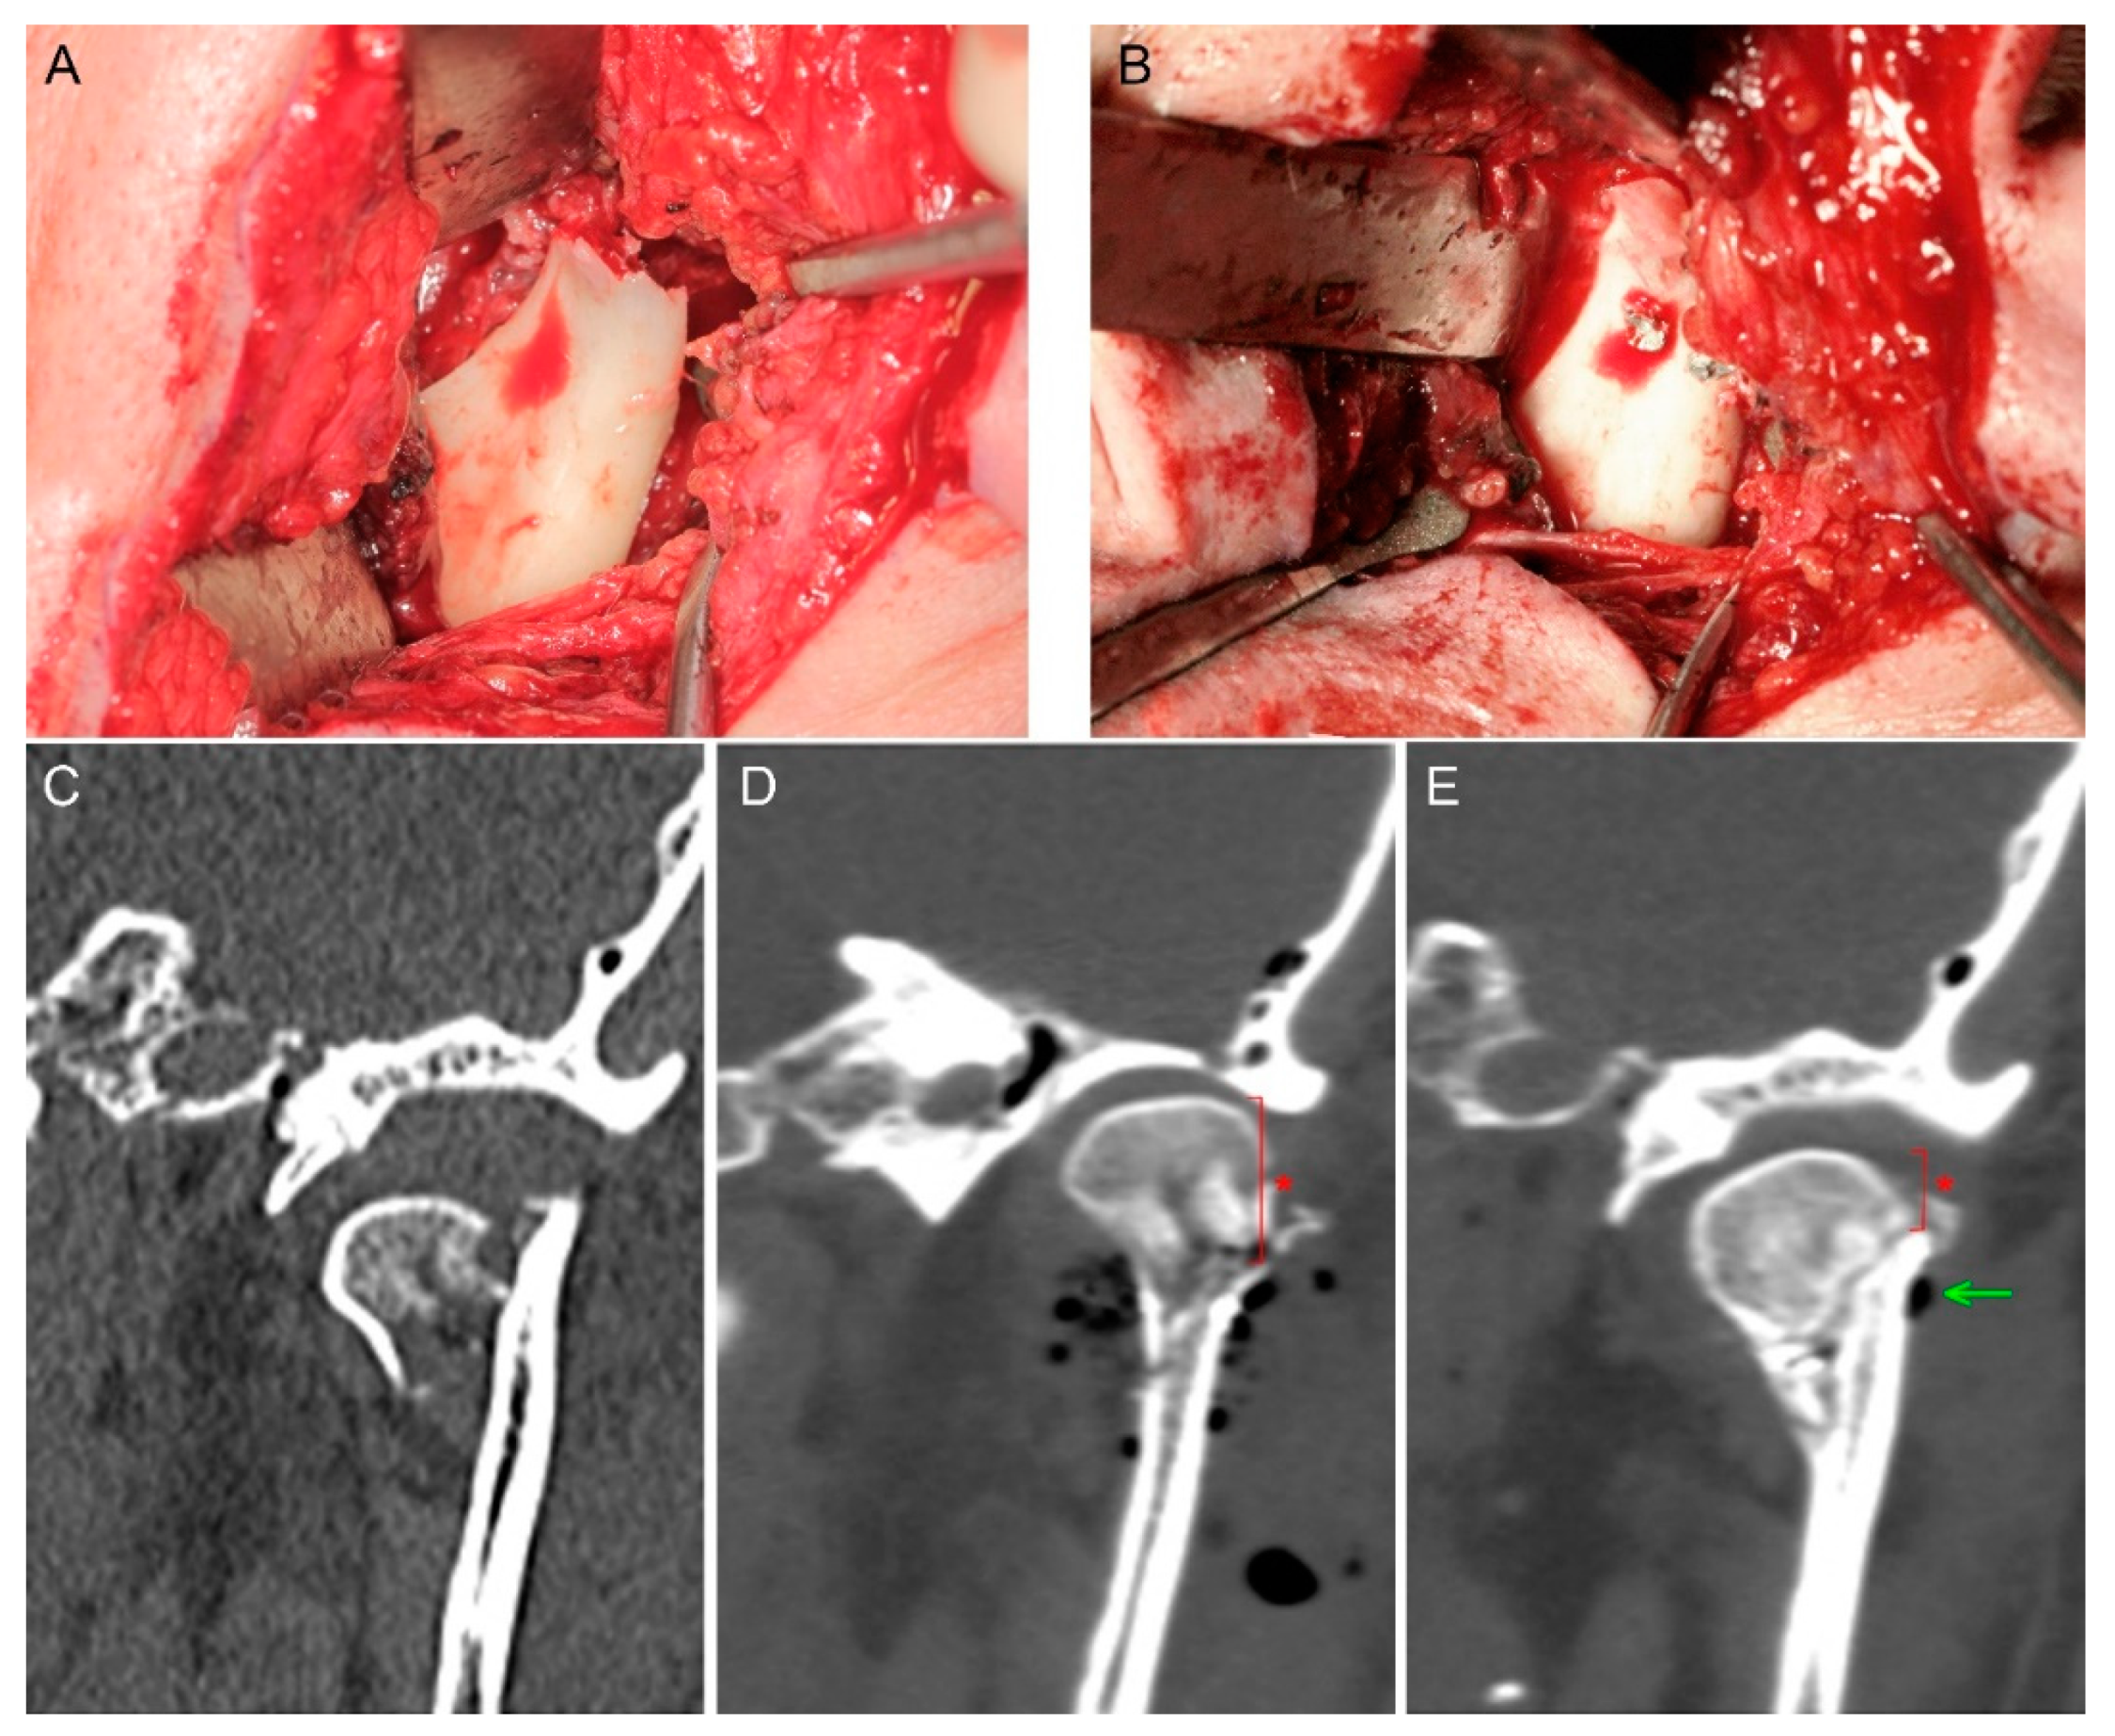

- Leonhardt, H.; Franke, A.; McLeod, N.; Lauer, G.; Nowak, A. Fixation of fractures of the condylar head of the mandible with a new magnesium-alloy biodegradable cannulated headless bone screw. Br. J. Oral Maxillofac. Surg. 2017, 55, 623–625. [Google Scholar] [CrossRef]

- Kozakiewicz, M. Small-diameter compression screws completely embedded in bone for rigid internal fixation of the condylar head of the mandible. Br. J. Oral Maxillofac. Surg. 2018, 56, 74–76. [Google Scholar] [CrossRef]